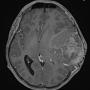

Temporal Ependymoma: A Case Study Emphasising Diagnostic Dilemmas and Therapeutic Challenges